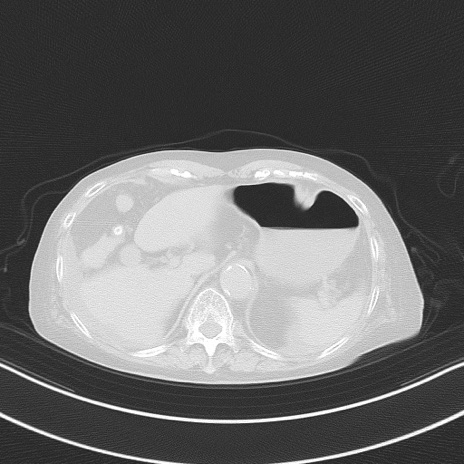

症例40(横断像)他院1日前

横断像

他院CT